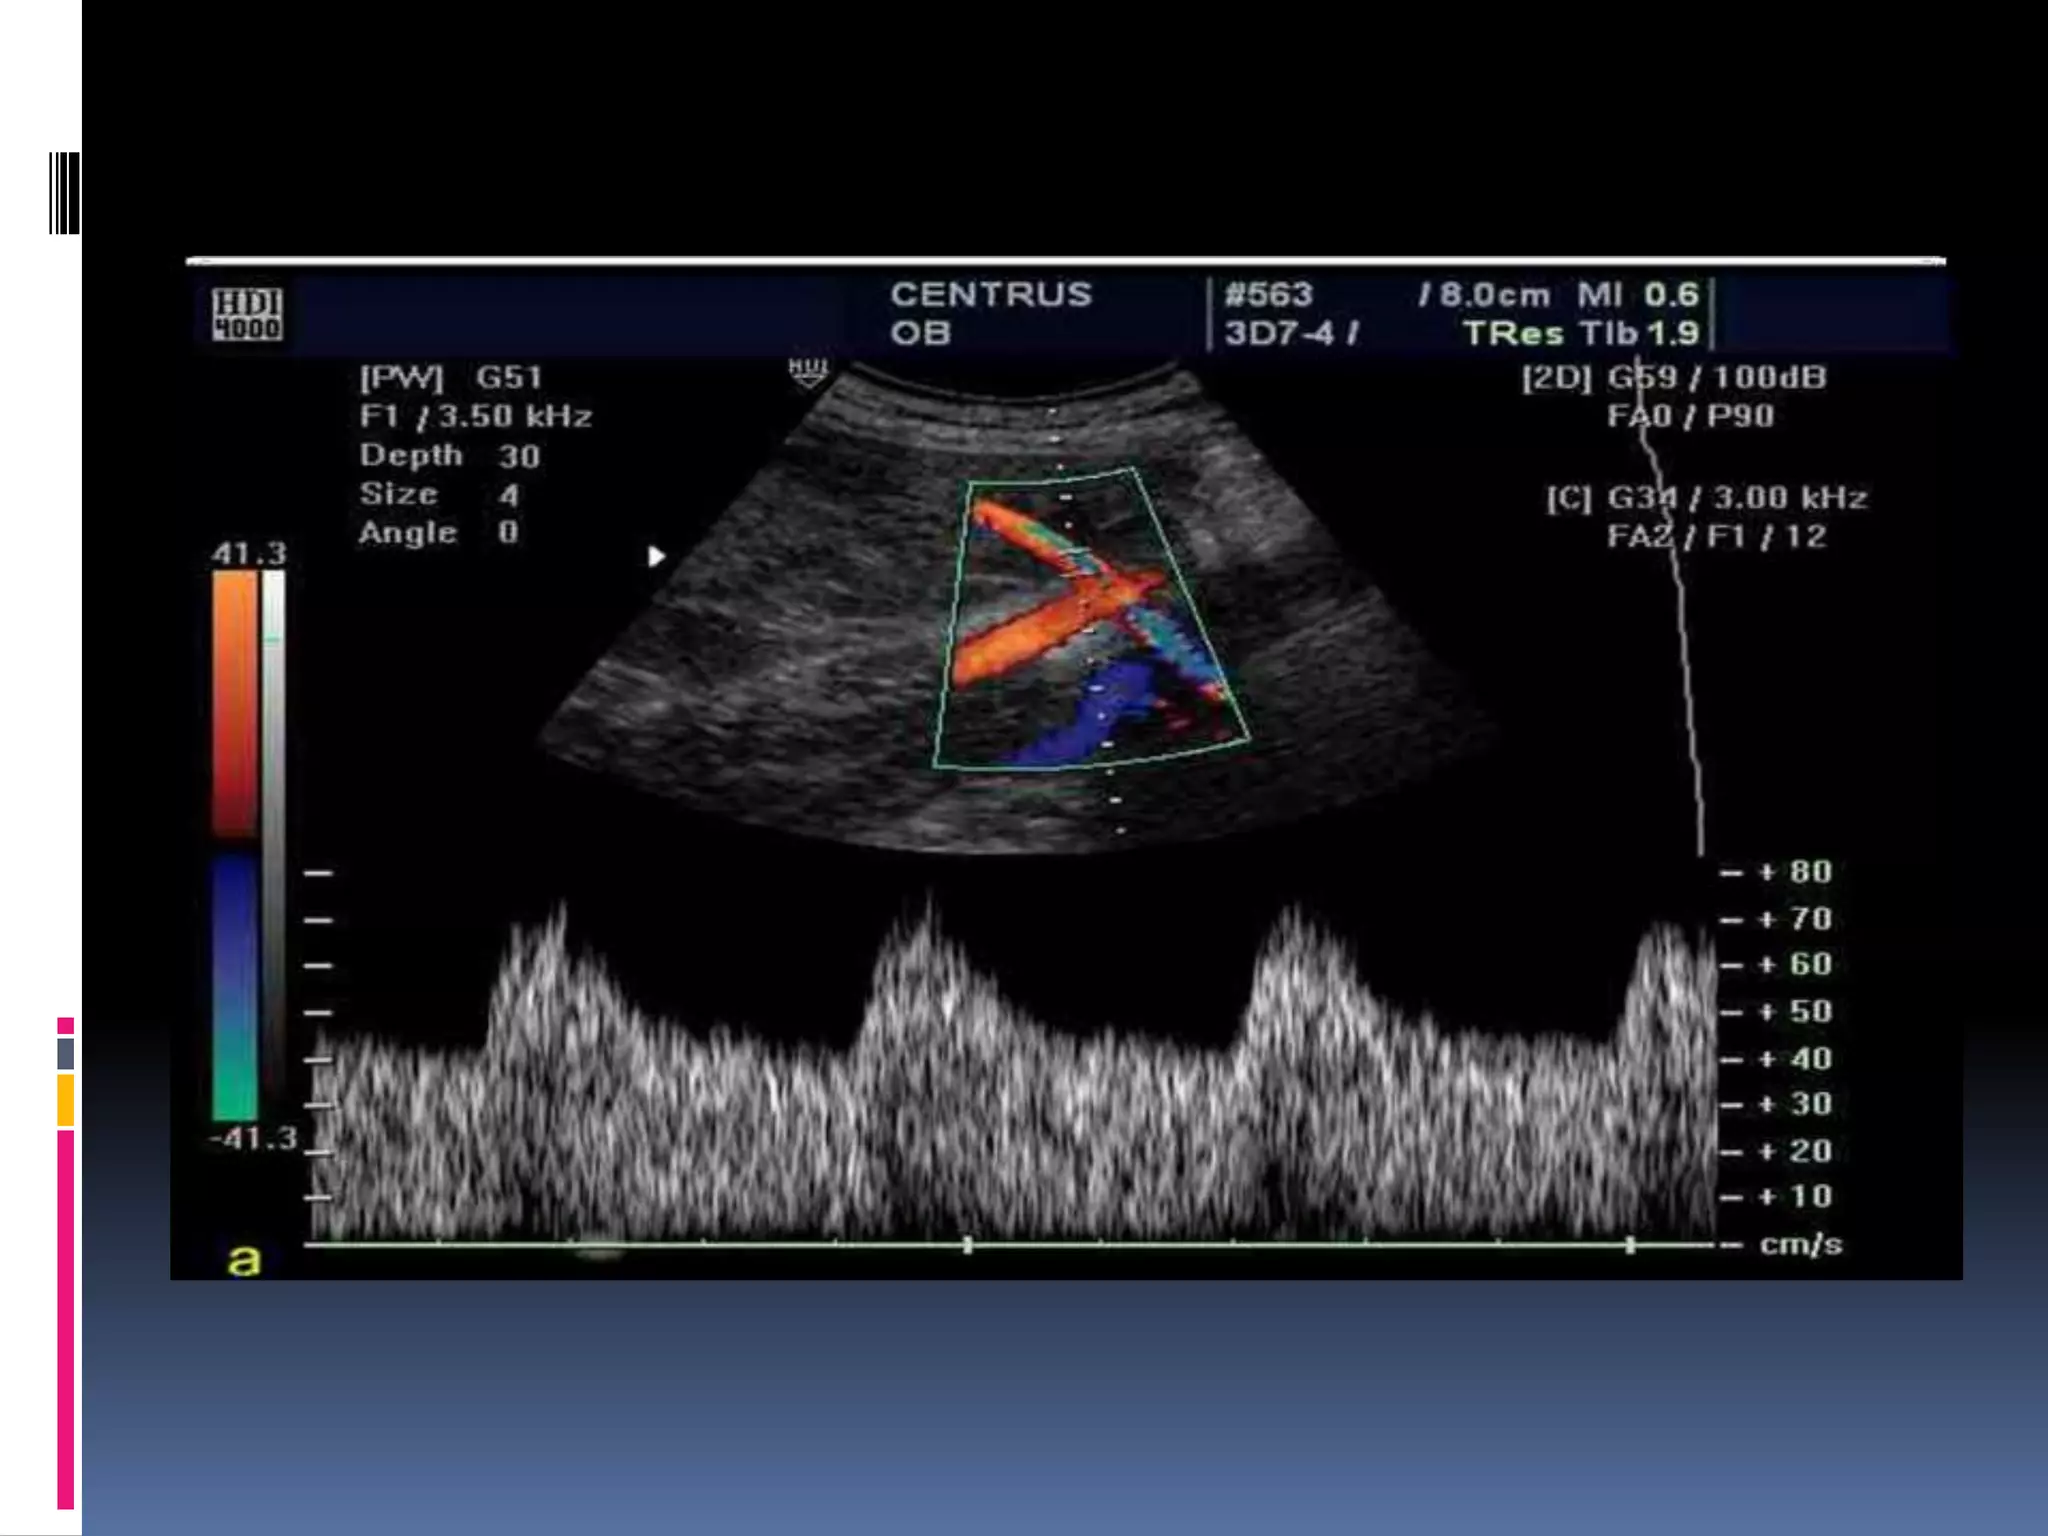

34 weeks viable fetus with normal umbilical artery blood flow.

 In the hypoxic fetus, the cerebral vasculature dilates

and this causes a reduction in the MCA pulsatility

index in a phenomenon known as “brain sparing”.

With disease progression the fetus is no longer able to